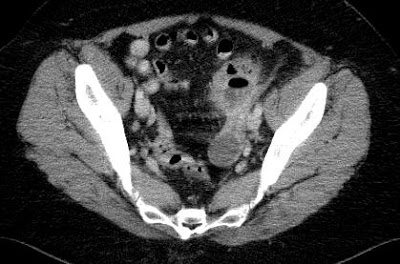

left tubo-ovarial abscess blowing the sigmoid wall

Tubular fluid-filled nonvascular structures in the pelvis that are associated with an adnexal mass are suggestive of dilated fallopian tubes that correlate with cases of pelvic inflammatory disease. A finding of an adjacent or surrounding complex mass confirms the diagnosis of TOA.